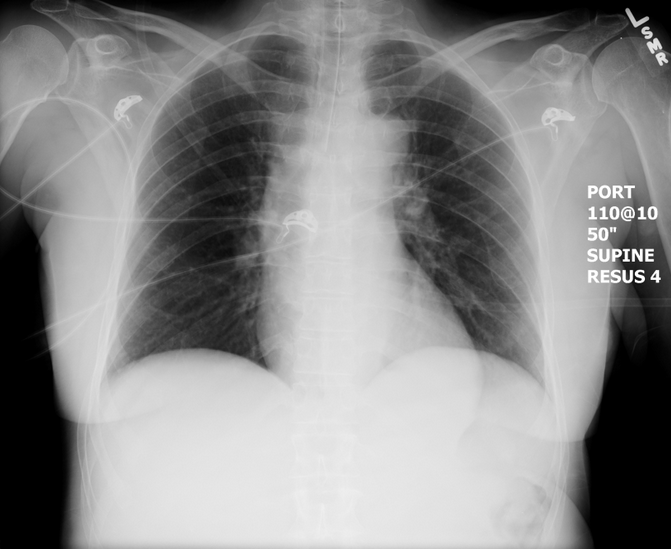

CXR for the case found here:

(CXR source: https://emcow.files.wordpress.com/2012/11/normal-intubation2.jpg)